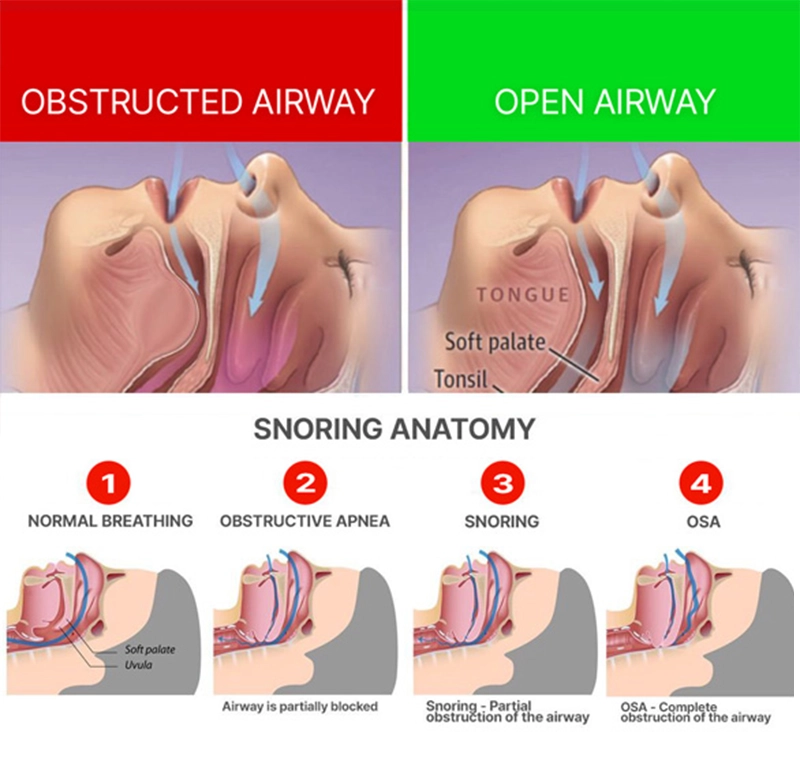

How does DreamHero function? Our body is naturally equipped to breathe via the nose during sleep. DreamHero, by subtly shifting your lower jaw, broadens your air passage, eliminating the root cause of snoring: tissue vibrations. Whether it's your peaceful sleep or that of a family member that snoring interrupts, let DreamHero guide you to rejuvenating mornings.

Snoring noise is caused by the soft tissue in your throat collapsing and creating turbulence as you breathe at night. The most effective snoring devices are mouthpieces that address this root cause by moving the lower jaw forward to open the airway. These mouthpieces can be made by a dental sleep specialist and can cost hundreds or thousands of dollars.

Sleep apnea is a more serious condition than simple snoring and should be managed by a qualified professional. Depending on the severity of the apnea, a mouthpiece to treat sleep apnea may be recommended for mild to moderate cases, or for people who cannot tolerate the use of a CPAP machine. Always discuss your condition and the best solution with a qualified specialist.